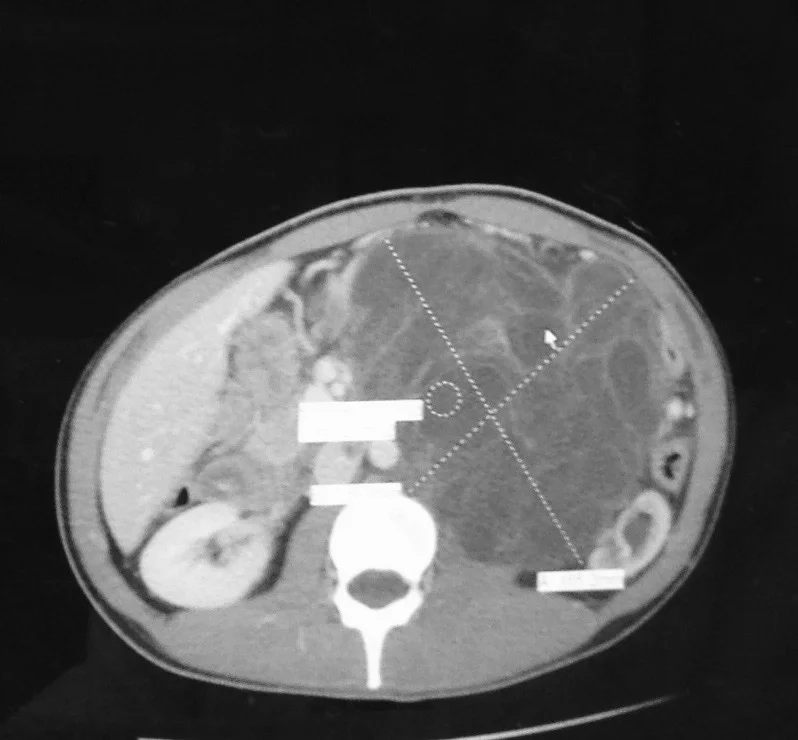

During Christmas break of Levi’s freshman year at Juniata College, he came home and said his back was hurting. He has never been one to complain, so I knew to take this seriously. We tried some basic things at home first, but then took him to urgent care and then to our family doctor a couple weeks later. Seeing a presumably “healthy” young man, he suggested that Levi should take a Tylenol and Ibuprofen cocktail and try stretching. Levi did what the doctor said and returned to school in January 2014. In a few weeks, he was in so much pain that he was taking 800mg of the cocktail 3x’s a day just to stay on top of it. During this time, he was attending all of his classes and doing his best to focus. Of course we took him back to the family doctor and I asked to be referred to a specialist so we could get some answers. Basically, we spent the next month going from doctor to doctor. Everywhere we went we were met with a pervasive cavalier attitude. Levi would explain the back pain and one after the other they would dismiss him. They took an x-ray, checked his blood, urine, blah, blah, blah…. At one point I said, “You aren’t listening to us. You don’t know my son. Something is wrong!” We were both completely frustrated. Levi was pushing and struggling just to get through each day. Finally, I called our family doctor-again- and demanded an MRI - NOW! I’m sure they thought I was an awful witch. Let’s just say, I didn’t ask nicely. The MRI and subsequent CT scan revealed that Levi had a 5” diameter mass growing in his abdomen that was pressing on his spine causing the back pain. By this time it was early March. The radiologist called us back to his office to show us the scans. He had our family doctor on speakerphone (yes, speakerphone) to give us the news. No one wanted to surmise what the mass was, so there was just a lot of silence.

His scans were sent to a doctor in Altoona, who promptly referred us to Pittsburgh. The specialist there told us that he could not be certain what we were dealing with until he removed the tumor and received the pathology report. He did however give us 2 scenarios. One- the tumor could be a harmless benign fatty mass, or two- a rare liposarcoma of the retroperitoneum. He stressed that he was leaning toward option #2 because, as an expert in this field, he has seen enough scans to know… He didn’t want to do a preliminary biopsy because if it was the type of soft tissue sarcoma he thought it might be, that would not be a responsible course of action. He warned us of the aggressive nature of the disease as the tumor was growing rather quickly, and scheduled Levi for surgery in early-April. If the tumor was indeed a sarcoma, radiation was to immediately follow. He also warned us of the possibility of it metastasizing to the lungs (as was typical for this type of cancer). Even though we had no pathology and only a CT scan as evidence, there didn’t seem to be a lot of hope in that room. The air was heavy and I didn’t like the way people were looking at me. I just remember that during that time everything was a blur. Surreal. It was so difficult to process what was happening. Of course Gary and I went home and read everything we could find online about that type of sarcoma. We did this everyday for weeks while we waited for surgery. We also prayed every single day that it was Option #1. One day we took a walk -to discuss it out of earshot of Levi- but we could barely speak of it. We just looked at each other. We knew it was bad and we were mentally preparing ourselves for the possibility of putting our son in the ground.

** The photo at the top is Levi's CT scan. It is a cross section of his abdomen and tumor. The big X is the tumor. It takes up over half of the space in his abdominal cavity. The white shape at the bottom of the photograph is his spine. You can see how squashed the kidney is by the tumor.